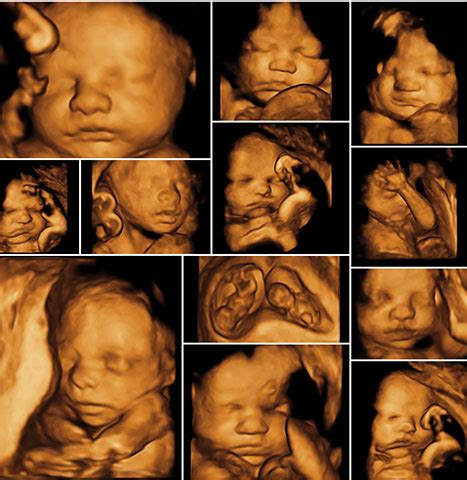

3D/4D ultrazvuk

3D ultrazvuk je skratka pre „trojrozmerné (trojdimenzionálne)“ zobrazovanie. Výsledkom je priestorový, nepohyblivý obraz štruktúry plodu. 4D ultrazvuk, na rozdiel od 3D ultrazvuku, predstavuje trojrozmerné zobrazovanie v reálnom čase. „Štvrté D“ v skratke „4D“ je „čas“. 4D ultrazvuk umožňuje vidieť v trojrozmernom zobrazení aktuálne pohyby plodu alebo jeho štruktúr. Pomocou 3D-4D zobrazenia môžeme lepšie posúdiť niektoré morfologické anomálie plodu.